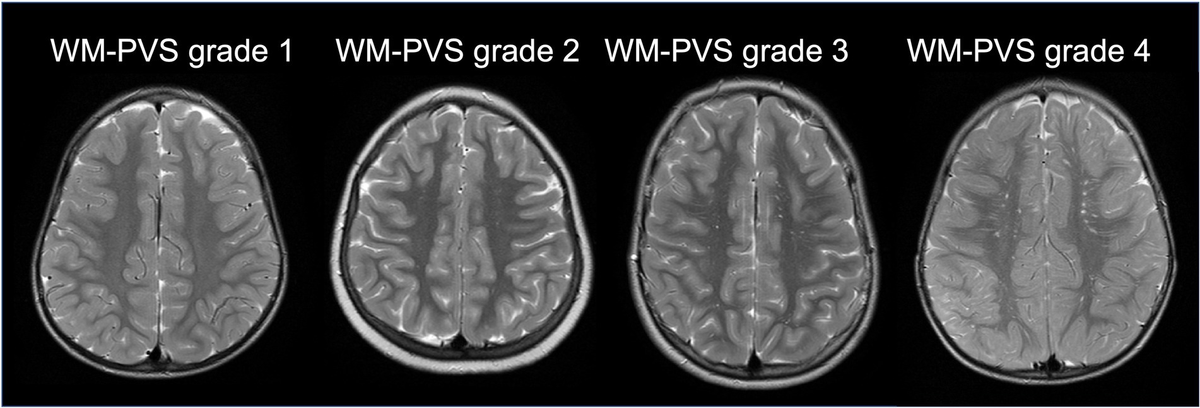

Wow, I wonder if autistic people often have low plasmalogens (after all, dayan goodenowe investigates this) and if any is connected with enlarged PVS

[maybe enlarged PVS can mean a lot of things - their connection with dementia risk is scary, but multi-etiology might mean there are multiple causes]